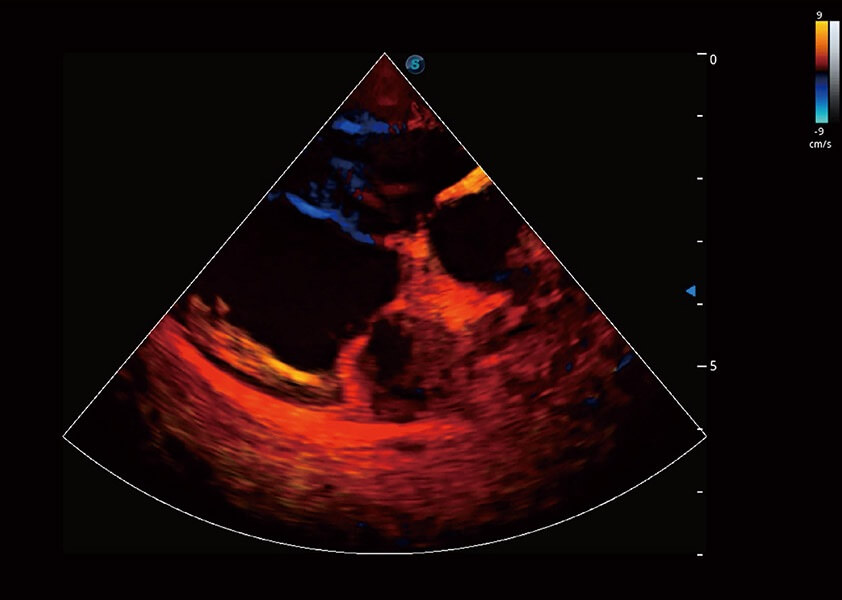

ProPet 60 作为一款高端台式动物超声设备,为动物医生的日常诊断提供了一系列贴合动物临床需求、解决临床实际问题的高级成像功能。凭借全系列高清探头,满足医生对腹部、心脏、生殖、浅表、肌骨等成像的所有需求,切实帮助您提升检查效率,提高诊断信心。

ProPet 60 尊享版

兽用彩色多普勒超声诊断系统